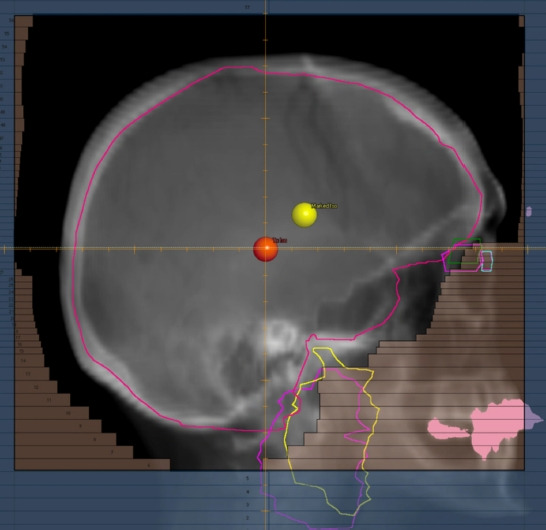

Purpose: Our purpose was to compare four whole brain radiotherapy (WBRT) delivery types: opposed lateral (OL) 3-dimensional-conformal radiotherapy (3D-CRT), a novel opposed lateral sparing (OLS) 3D-CRT technique, 3D optimized dynamic conformal arcs (optDCA), and hippocampal-avoidant WBRT (HA-WBRT).

Materials and methods: Ten patients previously undergoing HA-WBRT were retrospectively planned using OL, OLS, and optDCA techniques. OLS technique involved multi-leaf collimator (MLC) modifications to protect the lacrimal and parotid glands. OptDCA was inverse-planned 3D-CRT with dynamic conformal arcs. A dosimetric, cost, and resource utilization comparison was performed.

Results: Planning target volume coverage to prescription dose between 3D planning techniques was not significantly different between OL and OLS techniques (96.8% vs. 96.6%, p = 0.855), or between OL, OLS, and optDCA (95.0%) techniques (p = 0.079). There was no difference in the heterogeneity index between 3D plans (p = 0.482); all were less heterogeneous than HA-WBRT (p < 0.001). OptDCA was more conformal than OL and OLS, and similar in conformity to HA-WBRT. OLS achieved significant sparing of lacrimal and parotid glands over OL. There were significant step-function reductions in organ at risk (OAR) dose when comparing OL to OLS to optDCA to HA-WBRT plans. HA-WBRT was 57% more expensive than OL and OLS technique. HA-WBRT took approximately six times longer to plan.

Conclusion: We showed adequate and equivalent target coverage using OL, OLS, and optDCA techniques. Lacrimal and parotid dosages can be greatly reduced with the implementation of minor MLC adjustments. OptDCA therapy represented further improvement of these modifications, and was comparable to HA-WBRT in terms of OAR dose, while being about two-thirds the cost and more efficient to plan.